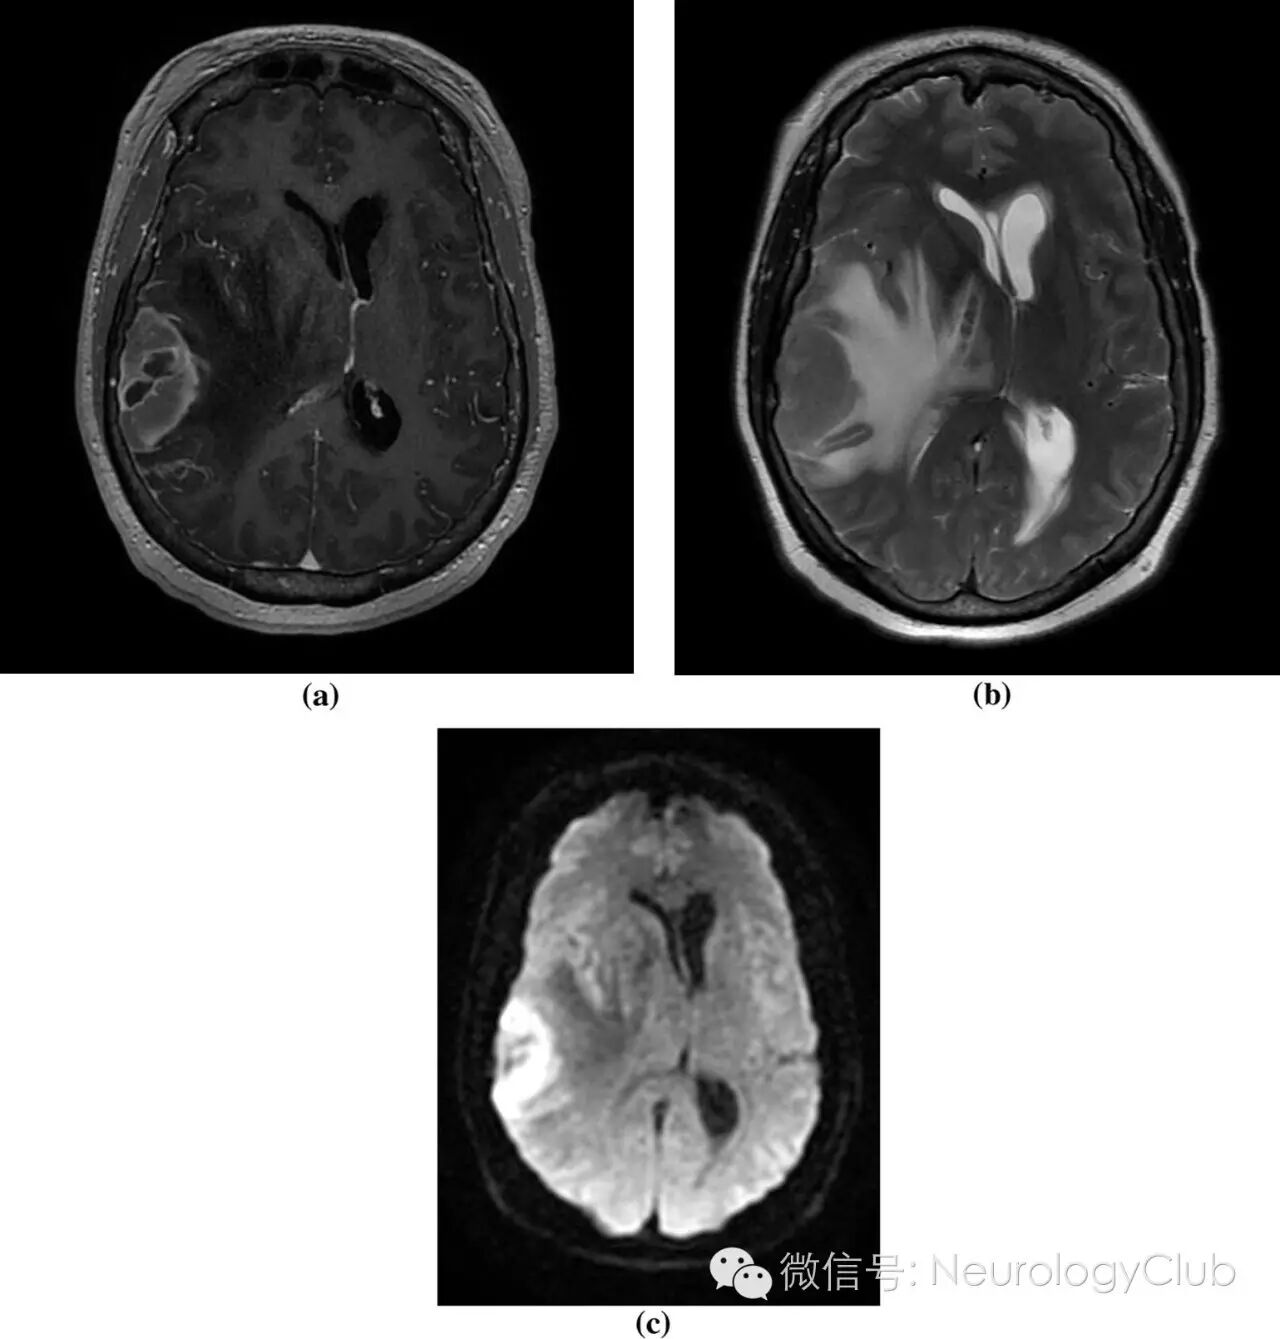

基于患者既往慢性髓系白血病病史和MRI表现,粒细胞肉瘤(绿色瘤)是最可能的诊断。给予激素和甘露醇减轻血管源性水肿。请放疗科和血液科会诊。患者行全脑放疗,并继续达沙替尼化疗。患者肌力逐渐改善恢复至两侧基本对称。7周后复查CT提示病灶对化疗和放疗效果明显(图3)。

(图3:复查CT提示右侧额颞叶病灶几乎完全消失)